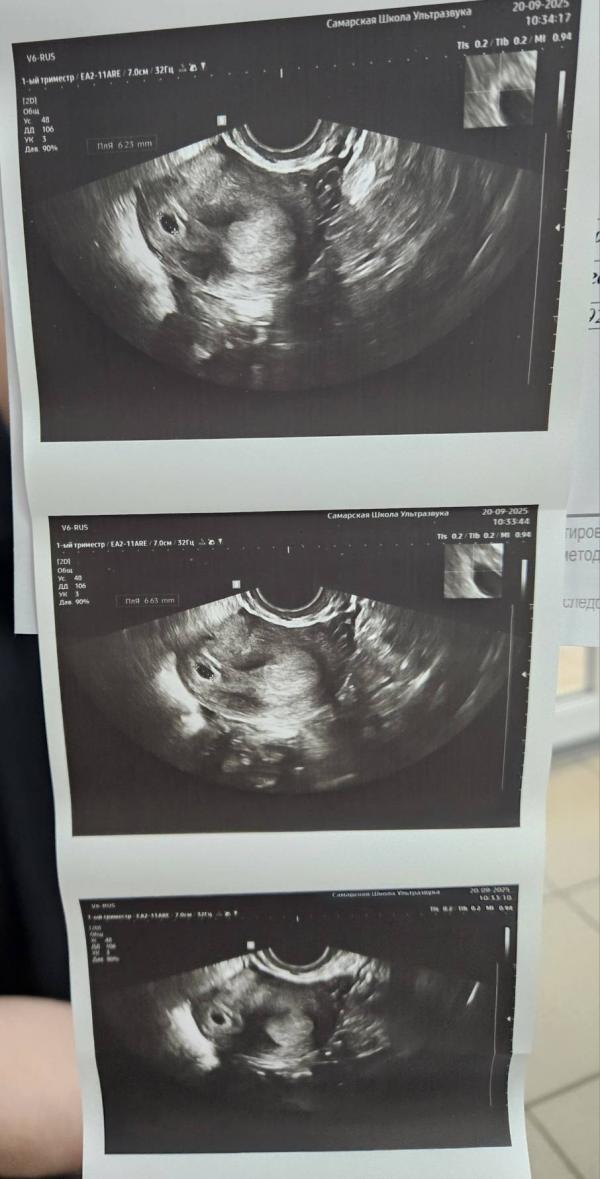

Вчера делали первое узи.

Врач поставила двурогую матку. Не особо понимаю, чем это все закончится. Первая беременность замерла на сроке 5,5нед и там меня измучили своими вердиктами: двурогая, седловидная, грушевидная, полип...

Через 2 недели пойдем на повторное узи искать сердцебиение ❤️